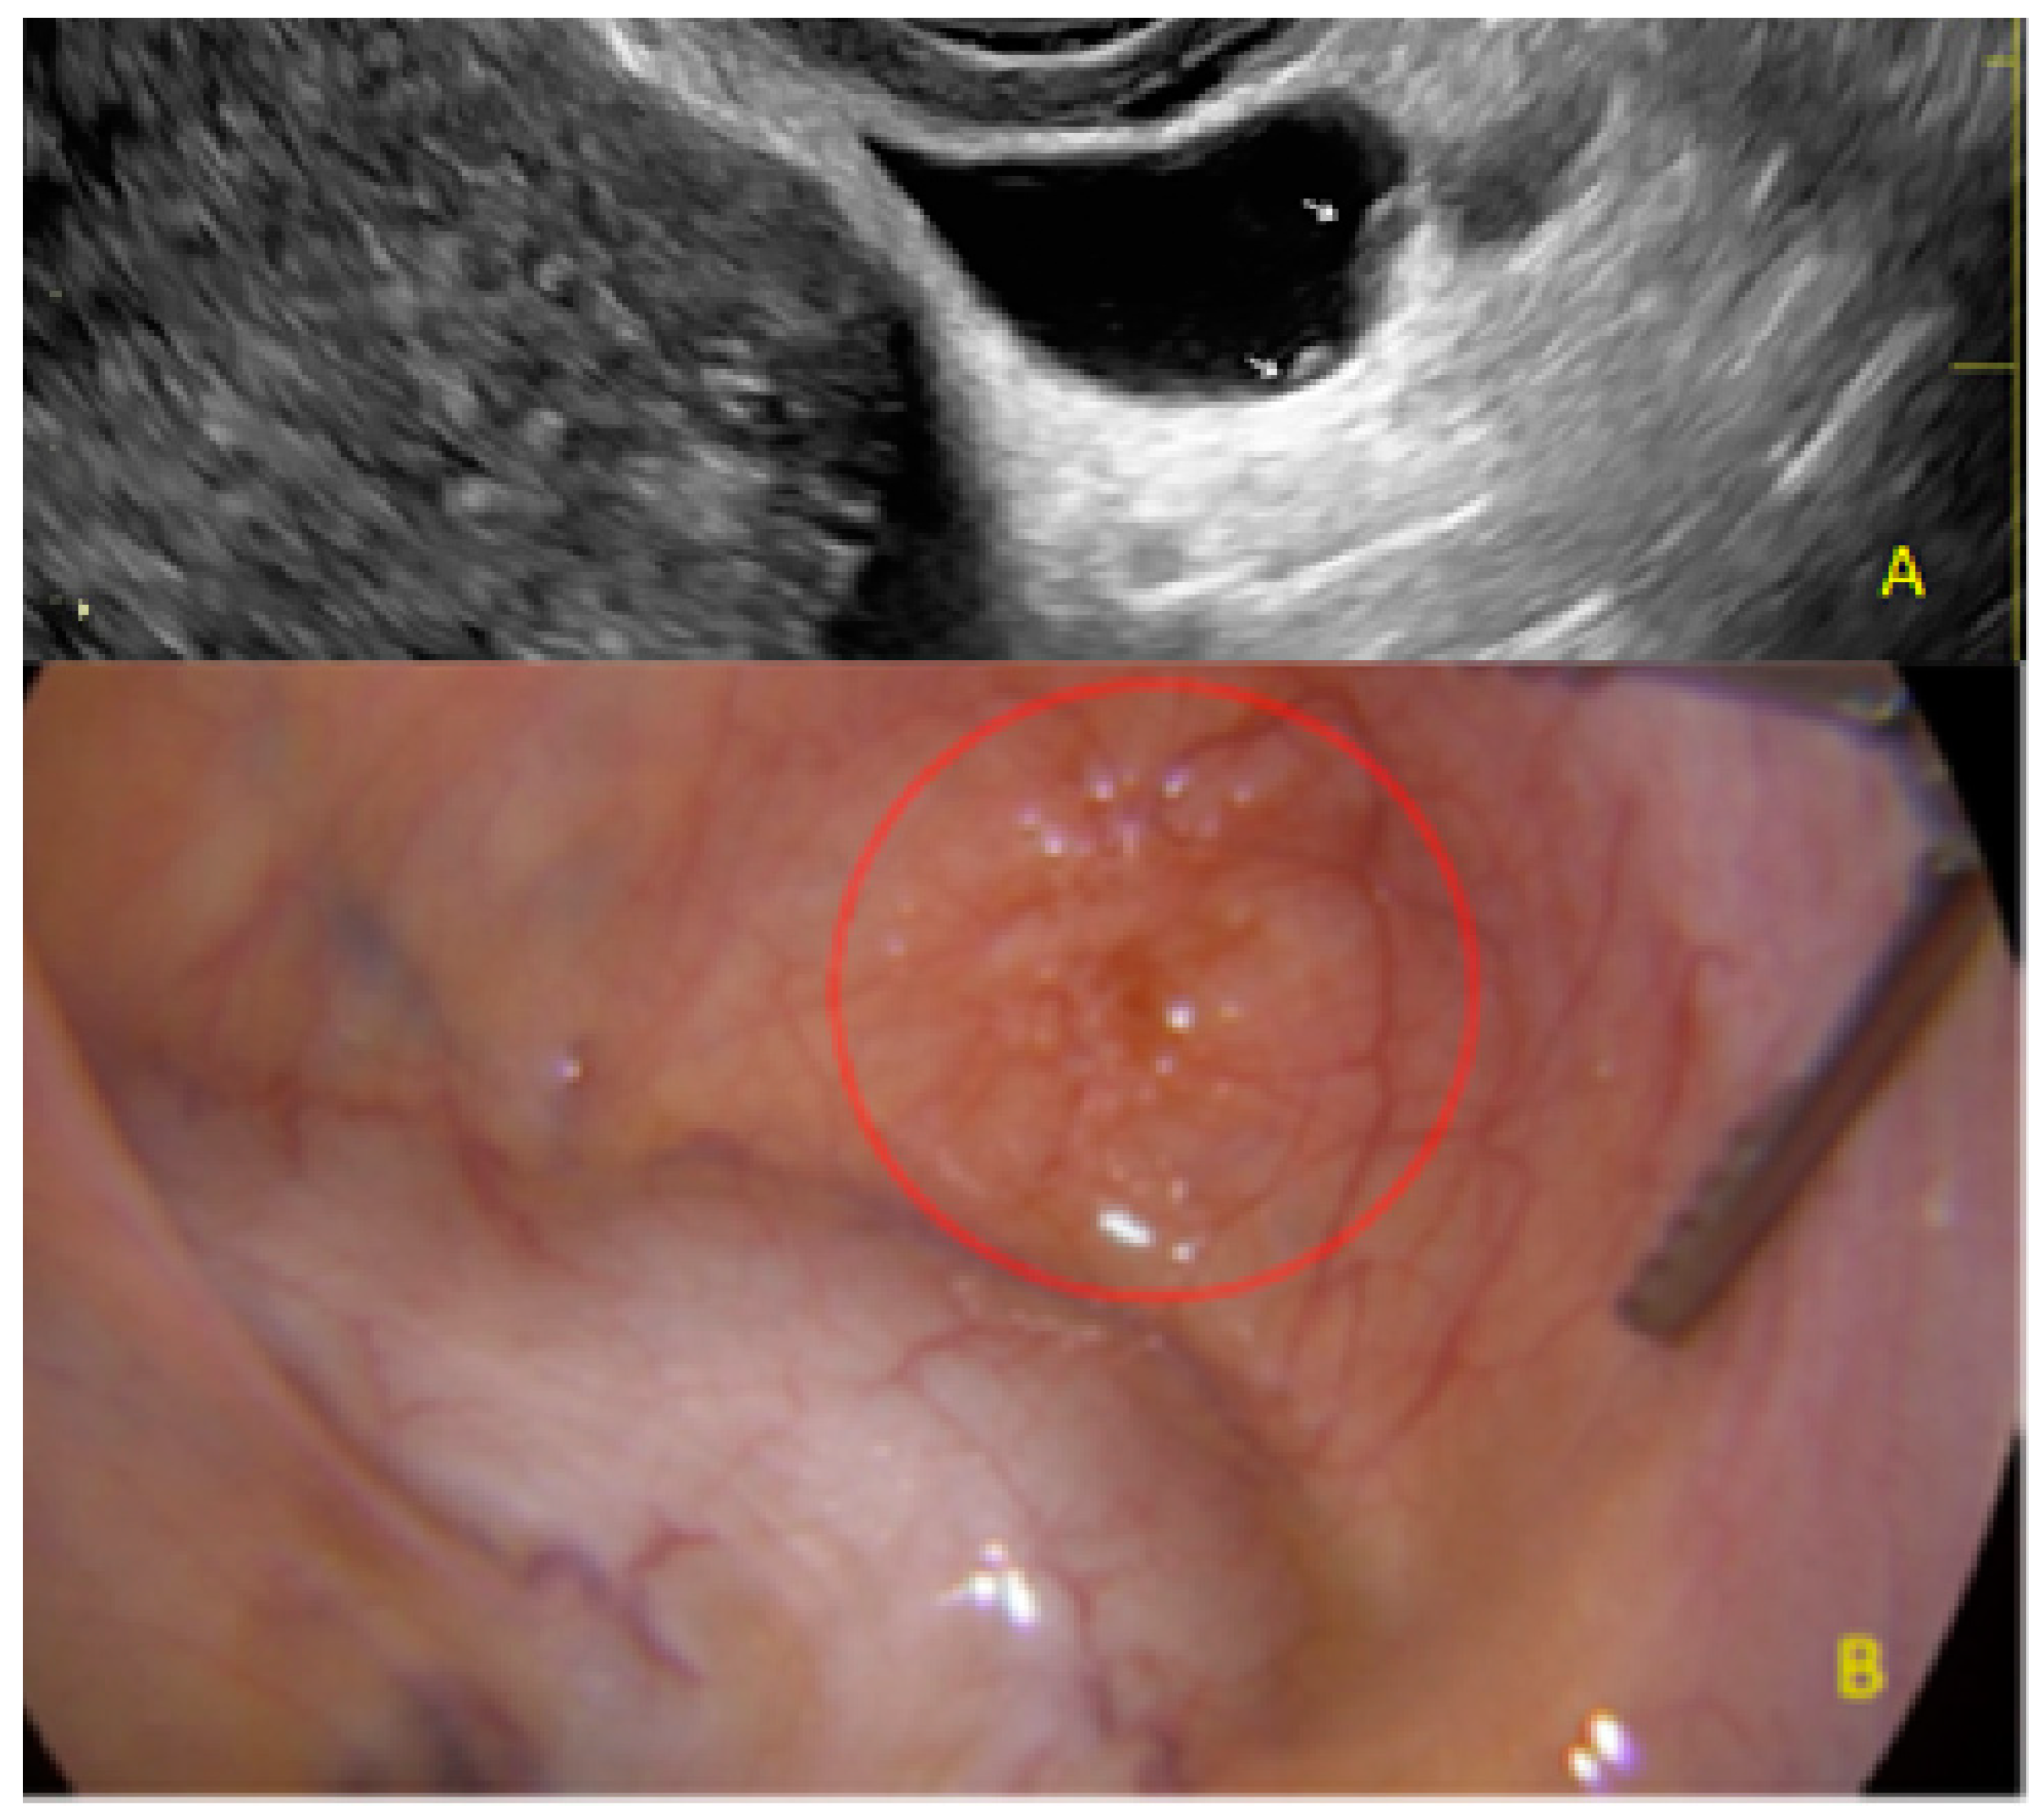

- The presence of hypoechogenic associated tissue (hypoechoic areas surrounding a small cyst area; we called this a “hat”). This tissue does not protrude or invaginate the peritoneal surface.

- The lesion may be convex, protruding from the peritoneal surface into the peritoneal cavity (we called this “bulging”), or it may appear as a concave defect in the peritoneum (we called this a “pocket”).

3.1. Cystic Solitary Lesion

3.2. Cystic Multiple Separate Lesions

3.3. Cystic Lesions Arranged in a Cluster